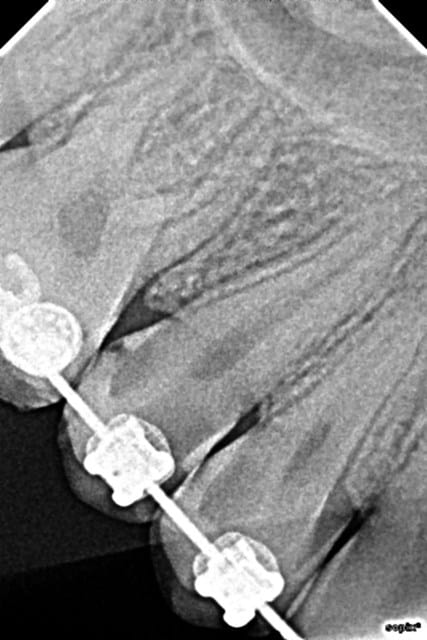

Fait hier sur une jeune demoiselle de 15 ans qui n'avait pas compris l’intérêt du brossage pendant son ttt ODF...

Facturé 45€ par dent en plus du compo, coté HBFD010 NPC pour facturation.

Ca prend du temps, c'est pas payé mais c'est satisfaisant dans ces circonstances... je n'avais pas envie de lui faire 2 endos à son age...

6 ujy5rd - Eugenol

8 jpznat - Eugenol

2 vzwmai - Eugenol

3 veiykt - Eugenol

Nb: joli boulot dent2669